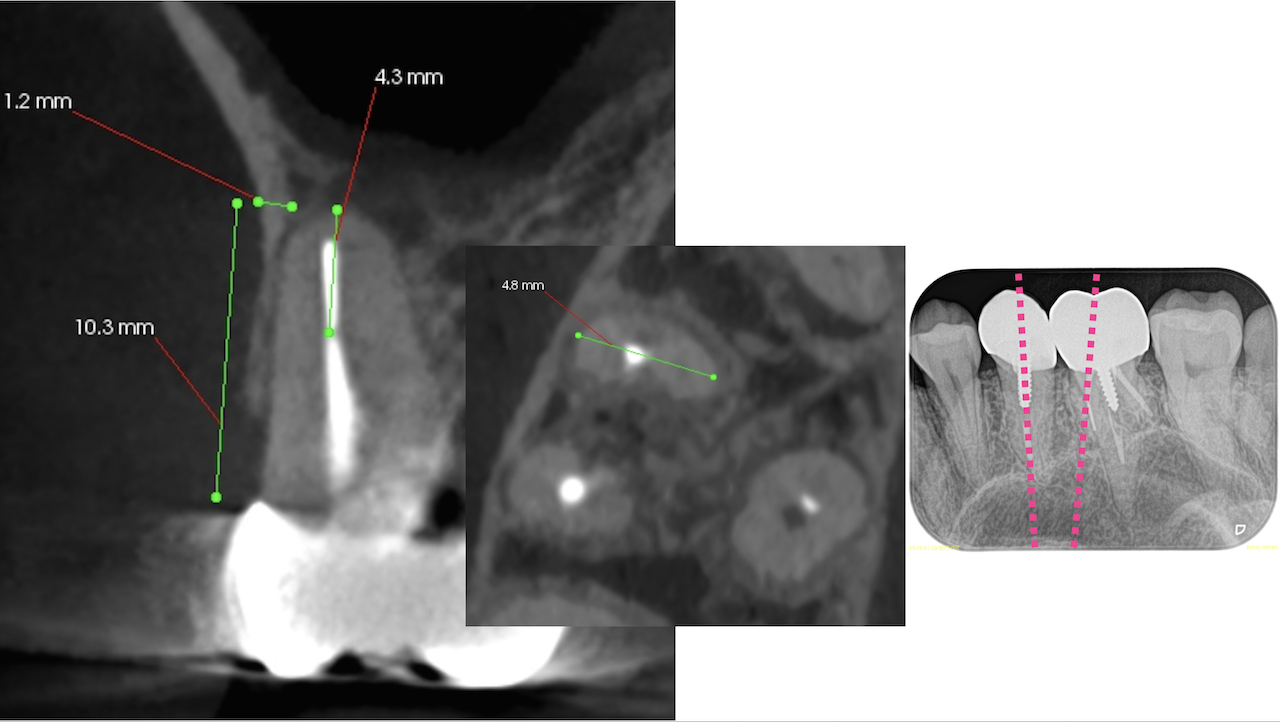

#3に関してだが、MBの破折ファイルはちょうどカーブの変曲点を超えて根尖部に折れ込んでいる。

この時点で、それをいかにして除去するか?よりも、FileごとApicoectomyしたほうが時短になると私は考える。

CEJよりも10mm下方にMBのApexがあり、

破折したファイルごと除去しようと思えば3mmでなく4.5mmApexから切断したほうがいいだろう。

この破折ファイルが除去できようが出来なかろうが治療の予後には全く影響を与えない

Recommended Tx: MB Apicoectomy